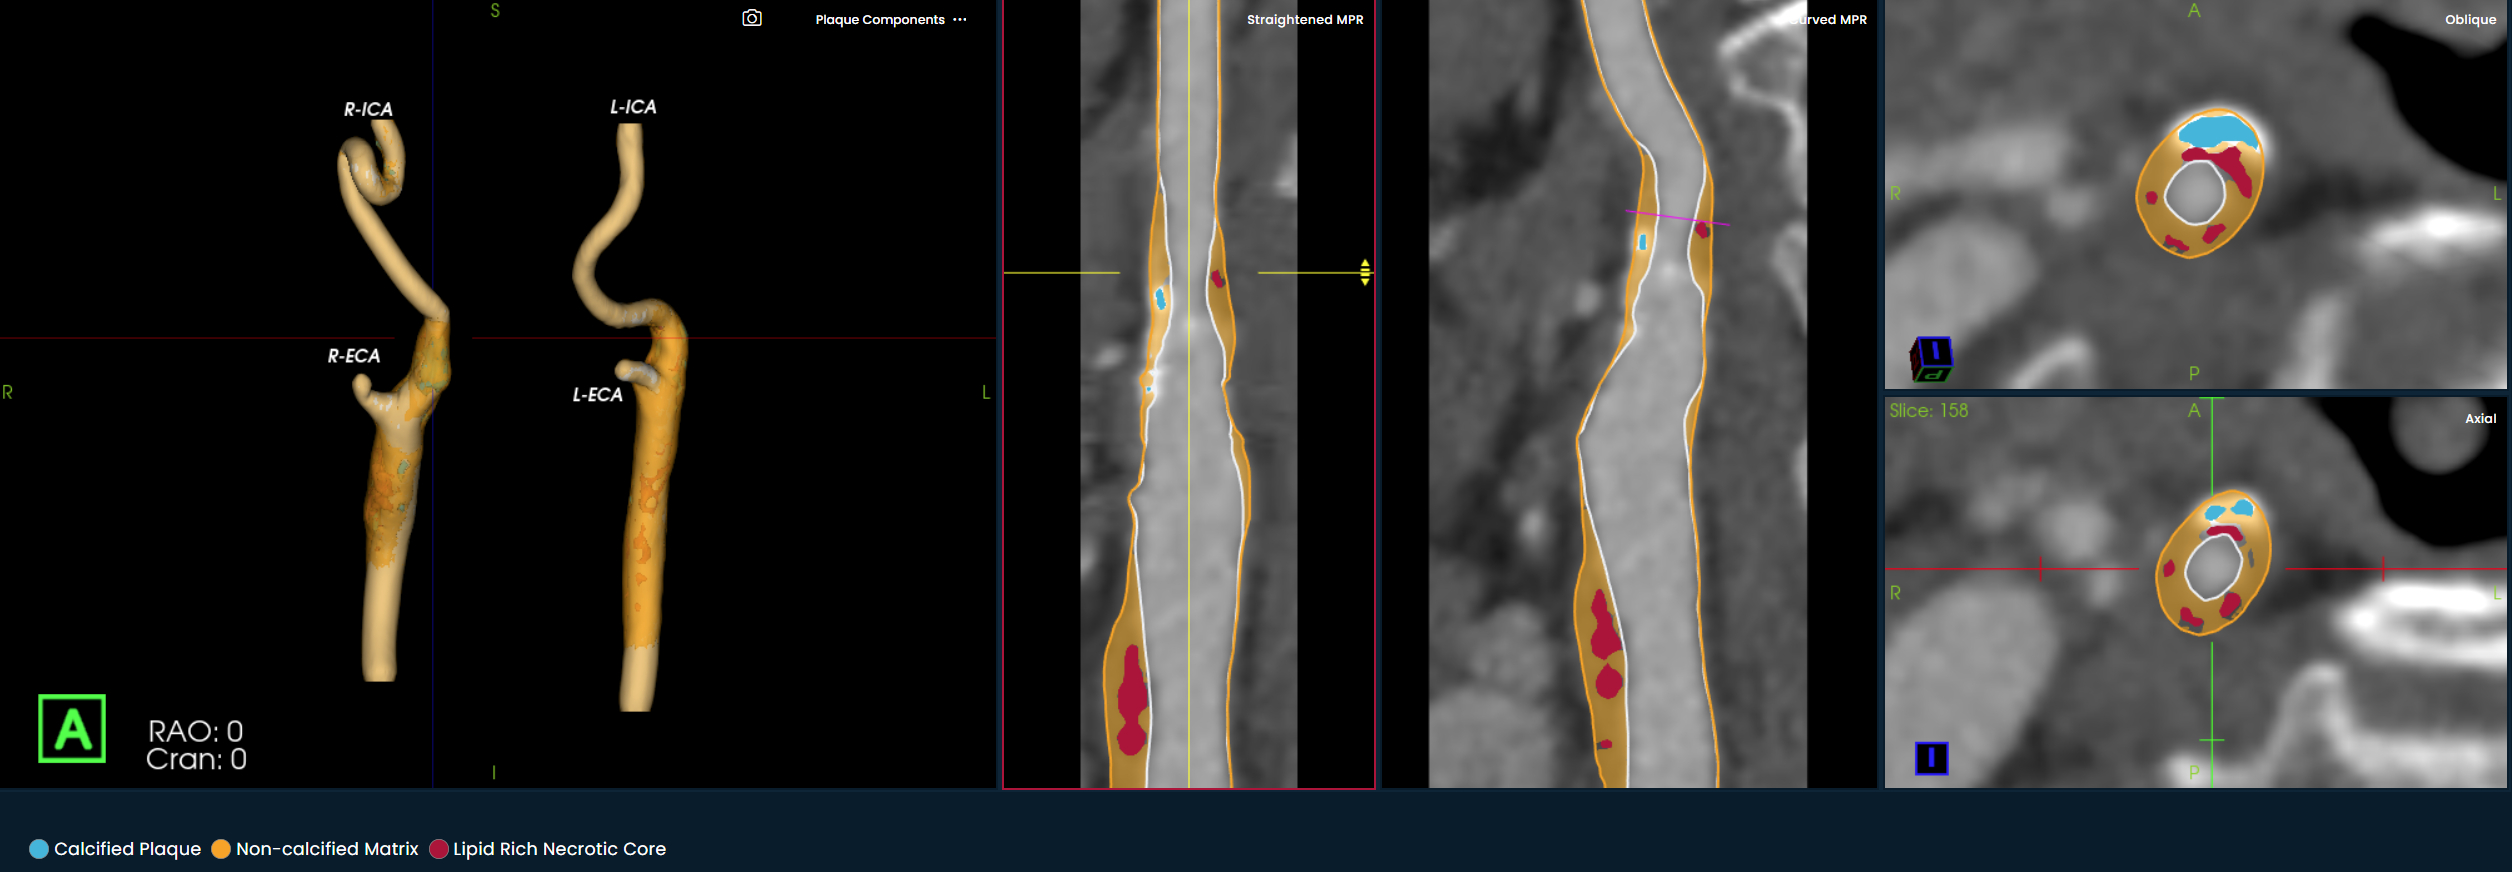

The Elucid PlaqueIQ (Source: Elucid)

BOSTON — Elucid, an AI-driven medical technology company dedicated to providing physicians with more precise insights into atherosclerosis for patient-specific treatment decisions, announced the launch of PlaqueIQ, a new image analysis software for quantifying and classifying plaque morphology in the carotid arteries. PlaqueIQ is the first and only CT-based plaque analysis software indicated for the carotid vasculature and is designed to help physicians identify plaques at risk of rupture and develop personalized treatment strategies to prevent ischemic stroke.

PlaqueIQ introduces a breakthrough in stroke risk assessment by enabling non-invasive, histology-based analysis of plaque composition. The platform provides physicians with CT Virtual Histology, offering detailed quantification and classification of plaque morphology and the ability to identify lipid-rich necrotic core—the plaque type most strongly associated with cardiovascular and cerebrovascular events.

PlaqueIQ is the first FDA-cleared, non-invasive plaque analysis tool based on objective histology. It allows physicians to move beyond traditional population-based risk models and instead prioritize and personalize treatment based on individual plaque characteristics in both the coronary and carotid arteries. The technology assists clinicians in evaluating symptoms, assessing risk for future events such as heart attack or stroke, and creating personalized care pathways that reflect the biology of each patient’s disease.

When used together for coronary and carotid imaging, PlaqueIQ provides a unified, quantitative, and qualitative view of systemic atherosclerotic risk, enabling comprehensive vascular assessment through a single non-invasive scan.